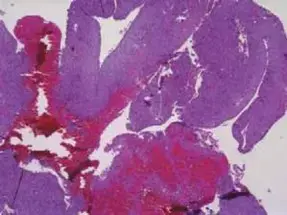

تعتبر الخزعة هي الطريقة الوحيدة لتأكيد التشخيص بشكل نهائي. في هذه الحالة، تم إجراء خزعة بالإبرة الموجهة بالتصوير المقطعي المحوسب (CT-guided core needle biopsy). يفضل هذا النوع من الخزعة لتقليل خطر تلوث مستويات الأنسجة وانتشار الخلايا السرطانية. كشفت الخزعة عن وجود خلايا غضروفية غير نمطية مع زيادة في الكثافة الخلوية وتعدد الأشكال النووية، مما يتوافق مع ساركوما غضروفية منخفضة الدرجة (الدرجة 1).